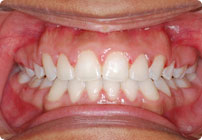

Despues

Caso: 11 años

Adolescente: Clase II

Mordida Cruzada Posterior

Sin extracción

Sin uso de expansores

6 alambres superiores

5 alambres inferiores

Sin uso de elásticos

Retenedores: Interior Fijo de TMA y Hawley en superior

Tiempo de tratamiento: 14 Visitas